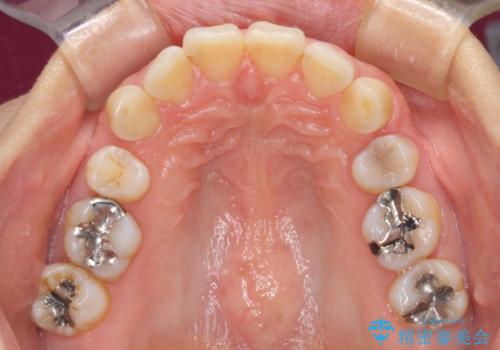

- 以前行った抜歯矯正が後戻りし、開いてしまったスペースが気になるとのことで来院された患者様です。

インビザラインを用いて開いてしまったスペースと前歯のデコボコを改善することとしました。

矯正治療後には気になっていた銀歯をセラミッククラウンやセラミックインレーにて治療することとしました。

上顎前歯を左右対称となるように歯列を整えたいとのことでしたが、すり減って形態が大きく異なっていたため、できる範囲での仕上がりとなりました。